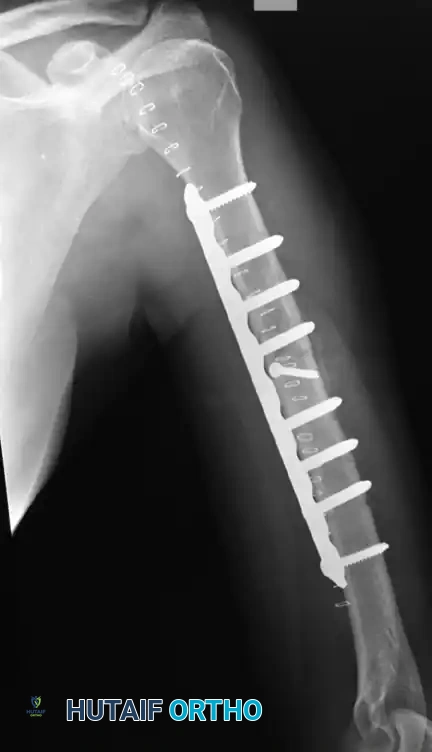

Figure 57-38 A: Segmental shaft fracture with extension into the proximal humerus.

Figure 57-38 B: Long plate utilized to obtain secure fixation across the segmental defect.

Figure 57-38 C: Lateral radiographic view demonstrating secure fixation with a long plate.